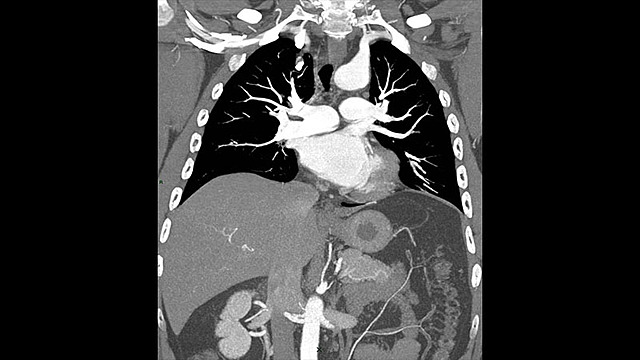

• TC en tórax

TC en tórax

Se utiliza para detectar:

1)Hemorragia intratorácica.

2)Enfermedades del corazón.

3) Émbolos pulmonares.